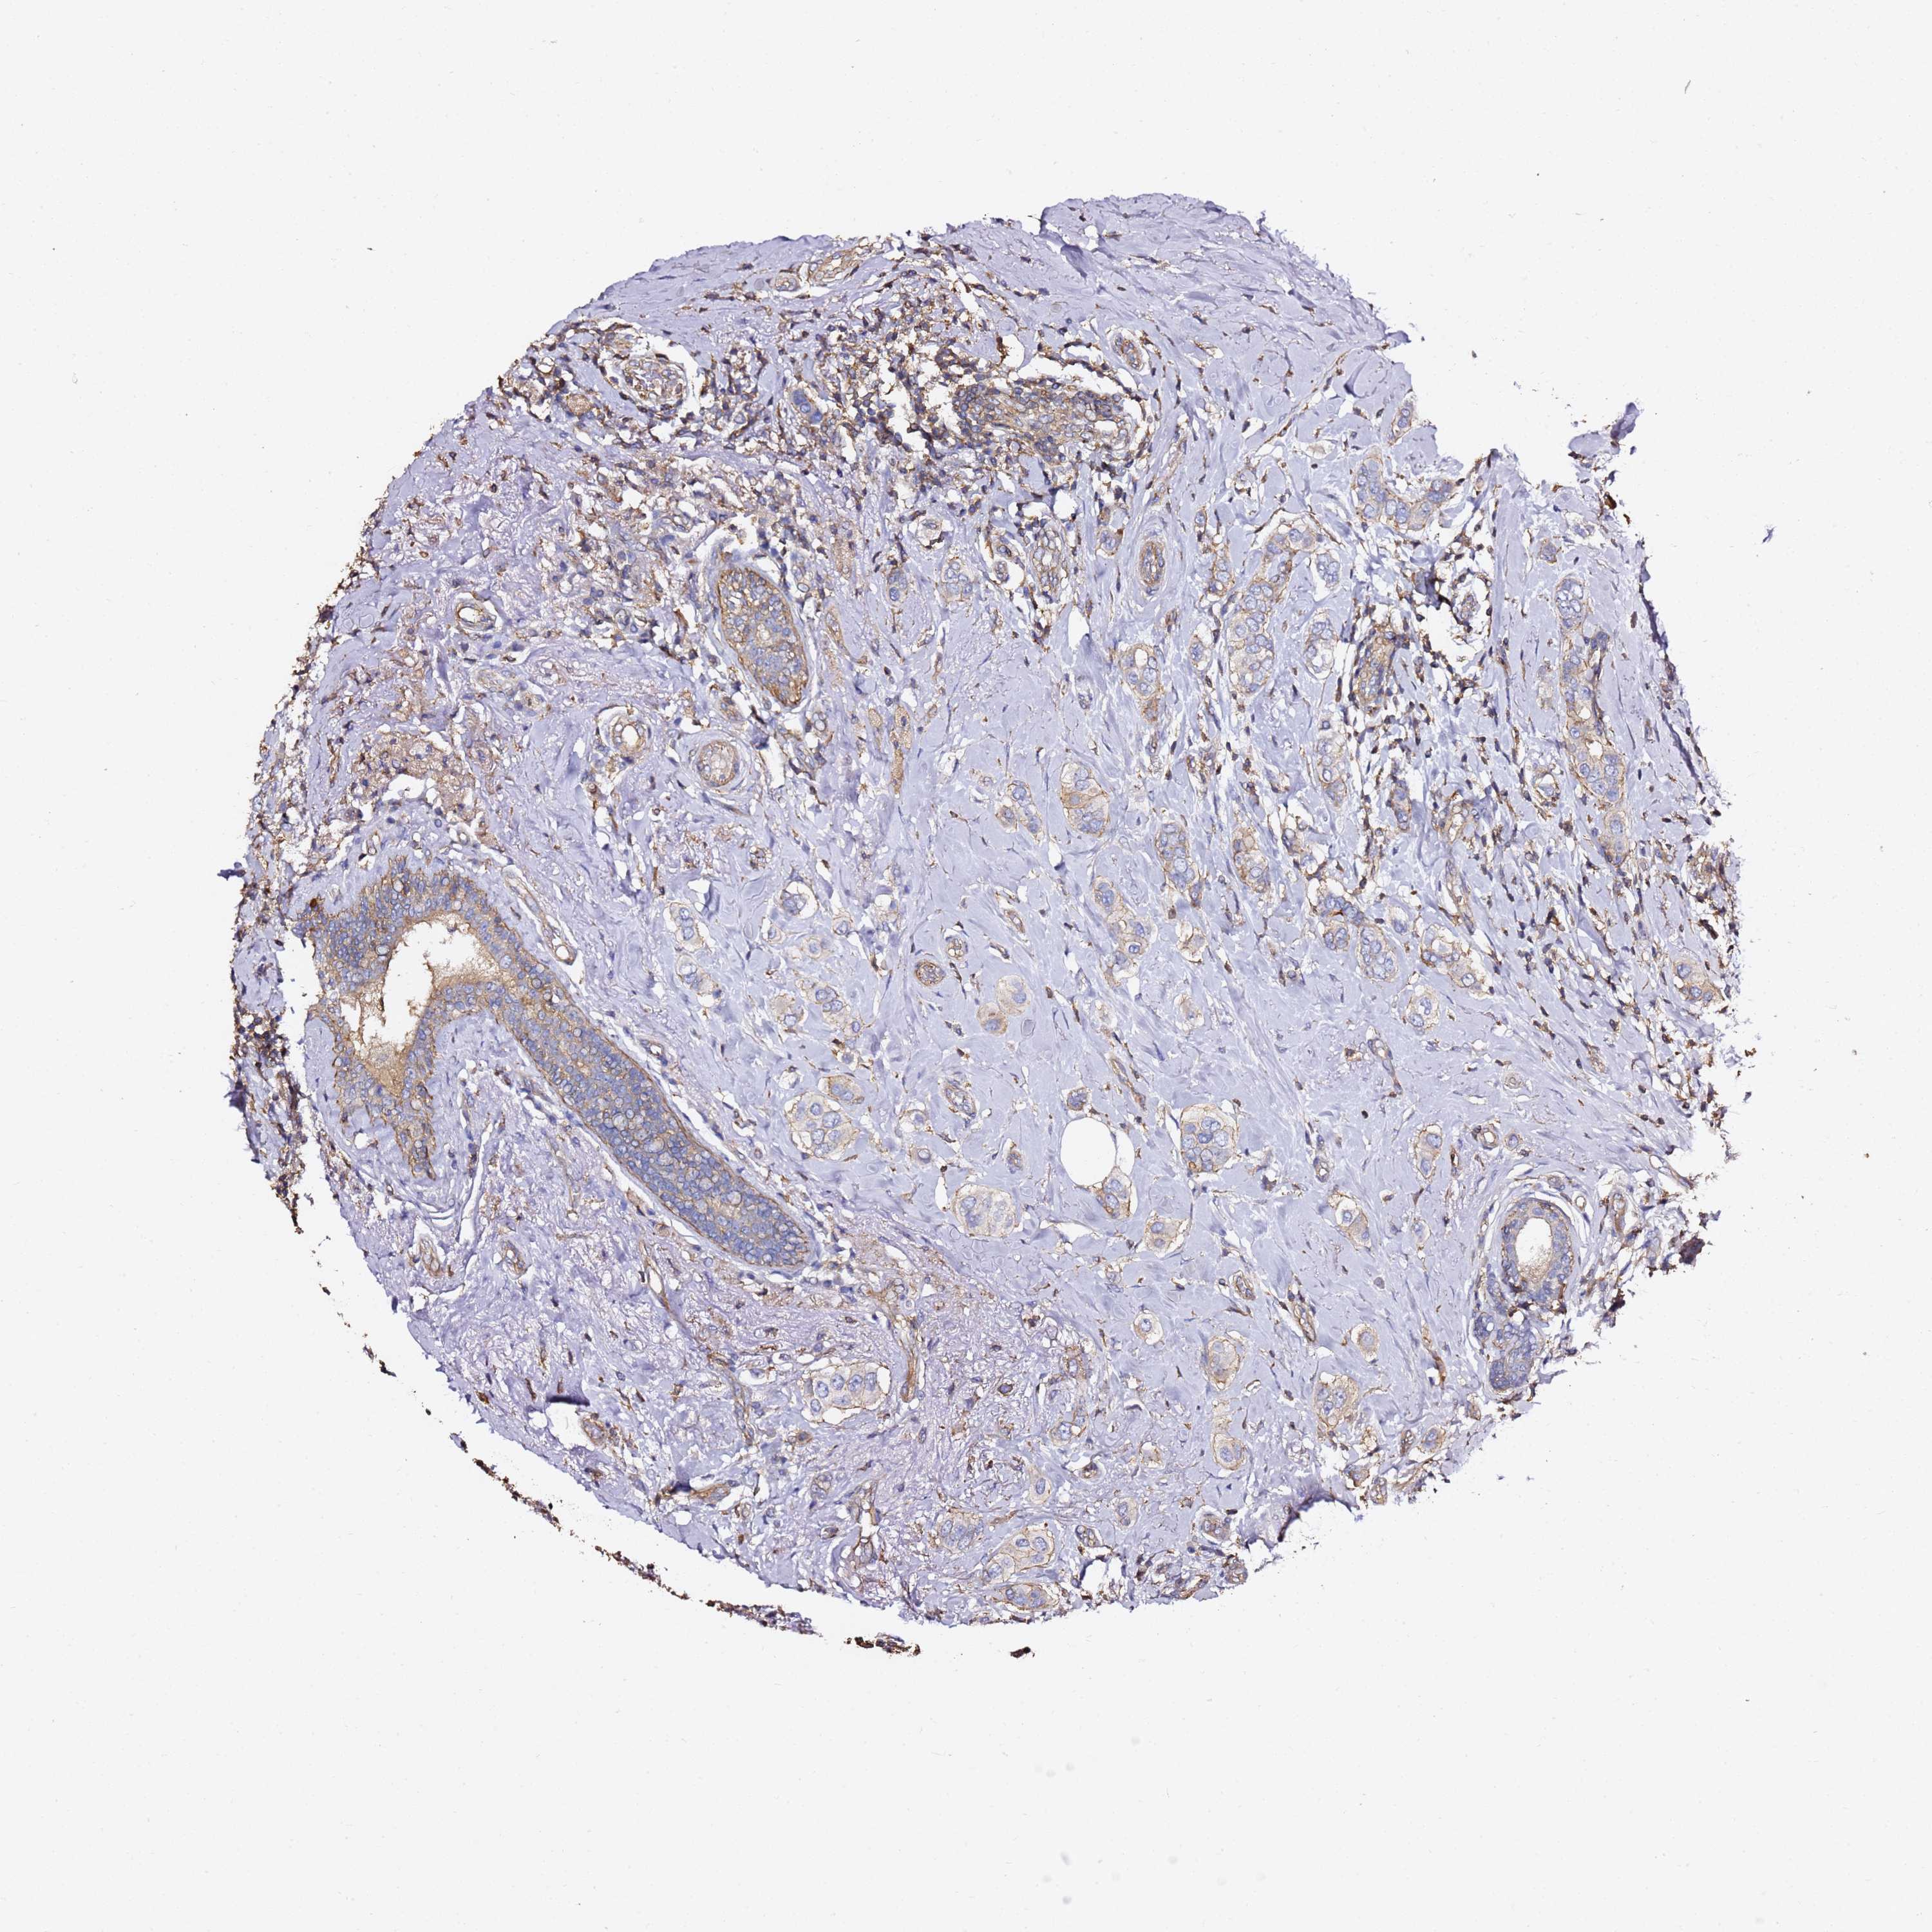

CANCER BREAST CANCER Show tissue menu

Breast cancer

Human cancer